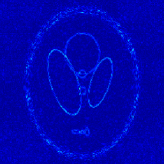

4.1 Phantom experiments

For the piecewise constant phantom experiments, we first compute the fully sampled k-space data using Eq. 3.1 with a piecewise constant function model Eq. 3.6. More precisely, given that ΩjsubscriptΩ𝑗\Omega_{j}’s are ellipses, Eq. 3.6 can be explicitly written as

where J1subscript𝐽1J_{1} is the first kind Bessel’s function of order 111. Then using the variable density random sampling method in [46], we generate 20%percent2020\% undersampled k-space data. The complex white Gaussian noise is also added so that the resulting SNR of the samples is approximately 25dB25dB25\mathrm{dB} (See Fig. 3).

Refer to caption

(a) Fully sampled

(b) Ground truth

(c) Sample mask

(d) Undersampled

Figure 3: Dataset for the phantom experiments. Fully sampled k-space data, its inverse DFT as a ground truth, the undersampling mask, and the undersampled k-space data.